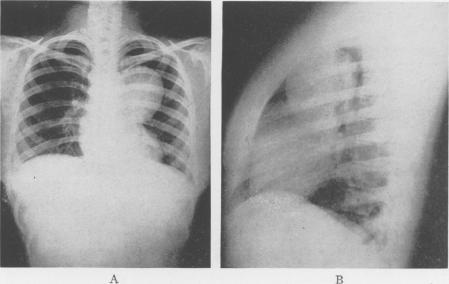

Bronchiogenic Cysts of the Mediastinum.

Ann Surg. 1948 Mar;127(3):476-502. doi: 10.1097/00000658-194803000-00010.